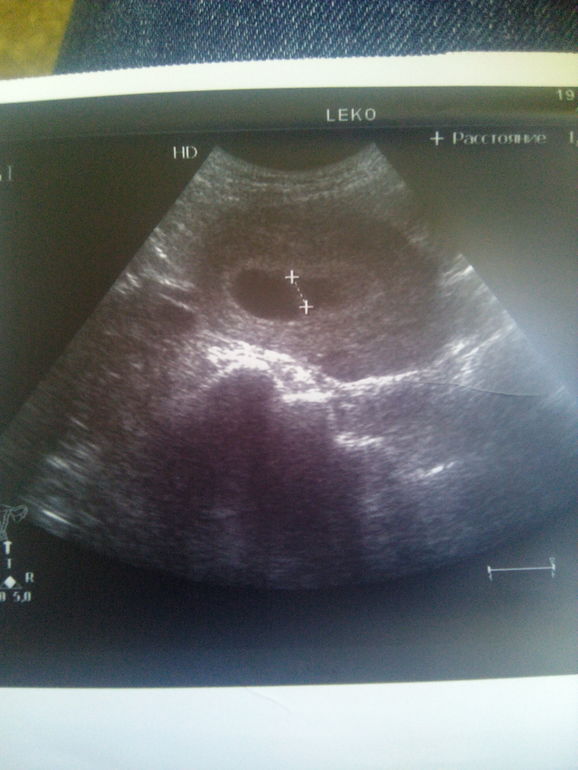

7+4 . Узи

Сходила я сегодня на Узи. Успокоилась пока немного. Пл 25 мм, ктр 10 мм. С/б +.